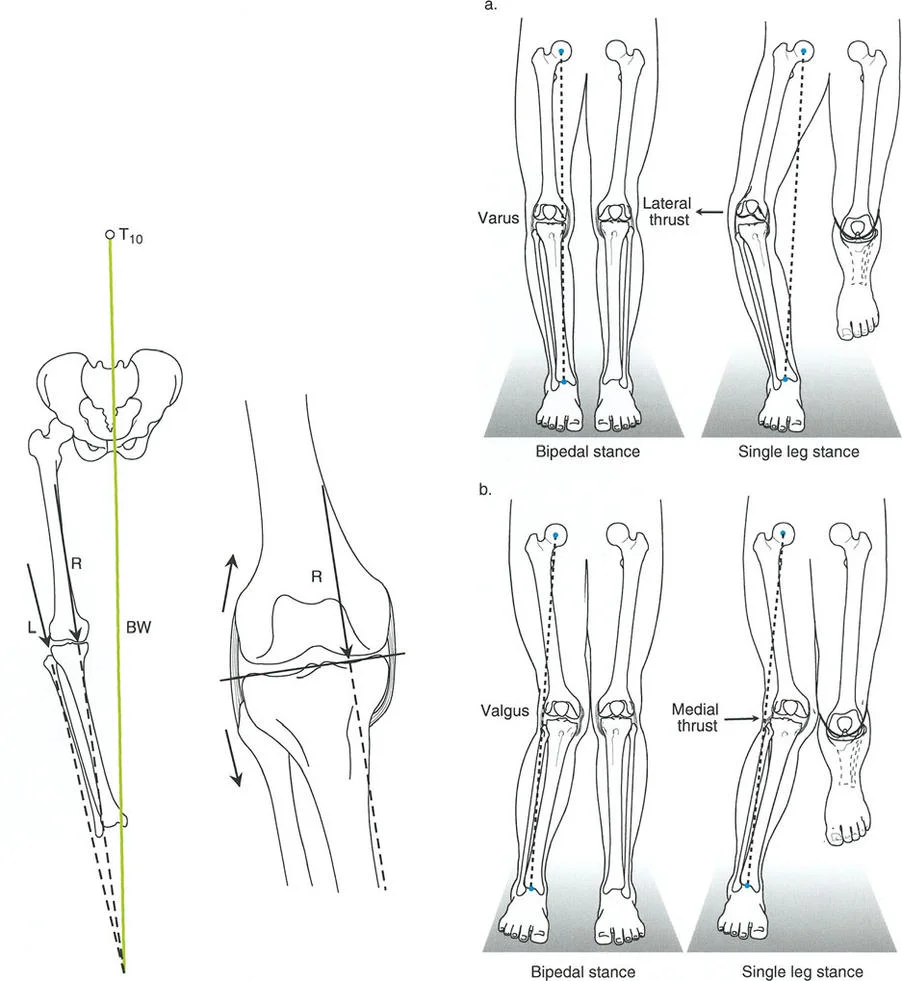

لذلك، ليس من المستغرب أن أي اضطراب في العلاقات التشريحية والميكانيكية الطبيعية في الطرف السفلي يمكن أن يؤدي إلى تسارع شديد في هذا التدهور التدريجي. نظرًا لأن الأطراف السفلية تحمل وزن الجسم طوال حياتنا، فإن المحاذاة المحورية للأطراف السفلية هي العامل الأكثر أهمية في تحديد المتطلبات الميكانيكية التي يتعرض لها الغضروف المفصلي بشكل متكرر خلال مراحل المشي الديناميكية.

المحور الميكانيكي للطرف السفلي هو خط مستقيم يمتد من مركز مفصل الورك (رأس عظم الفخذ) إلى مركز مفصل الكاحل. يمثل هذا الخط مسار انتقال قوة تحمل الوزن خلال الوقوف الثابت. أي انحراف في هذا المحور، حتى لو كان طفيفًا، يمكن أن يغير توزيع الأحمال على الغضروف المفصلي، مما يؤدي إلى تآكل متسارع.

انحراف المحور الميكانيكي (MAD): مقياس الضرر

بناءً على ملاحظات التشريح الطبيعي، تُعتبر مفاصل الطرف السفلي متوازية بشكل طبيعي. أي تشويه لهذه العلاقة يؤثر بشكل متوقع على نقل الأحمال. بينما يمكن لمفصل الورك (كونه مفصلاً كرويًا متطابقًا للغاية) أن يستوعب بعض التغيير في اتجاه الحمل، ومفصل الكاحل محمي بحركة تعويضية معقدة للمفصل تحت الكاحل، فإن الركبة معرضة بشكل استثنائي للتغيرات في المستوى التاجي. إنها مفصل مفصلي يعتمد بشكل كبير على أربطته الجانبية والغضاريف الهلالية لإدارة الأحمال غير المتساوية.

عندما يؤدي تشوه المستوى التاجي إلى اختلال المحاذاة المحورية، فإن محور تحمل الوزن يمر إما وسطيًا أو جانبيًا لمركز الركبة. تُقاس القيمة المطلقة لهذا الانحراف باسم انحراف المحور الميكانيكي (Mechanical Axis Deviation - MAD).

كيفية قياس MAD:

- ارسم المحور الميكانيكي للطرف السفلي (خط مستقيم من مركز رأس الفخذ إلى مركز سطح الساق).

- ارسم قطعة خطية عمودية تمتد من خط المحور الميكانيكي هذا إلى المركز الهندسي الدقيق لمفصل الركبة (نقطة المنتصف بين شوكتي الساق).

- طول هذه القطعة العمودية، المقاس بالملليمترات، هو MAD.

يعكس حجم MAD بشكل مباشر حجم نقل الإجهاد المتغير عبر الركبة. يُعد قياس MAD متفوقًا بشكل كبير على مجرد قياس الزوايا الإجمالية للطرف لأنه يأخذ في الاعتبار التشوهات من أي نوع — بما في ذلك الدوران، الانتقال، والزاوية — ويترجمها إلى قيمة ميكانيكية حيوية واحدة ذات صلة سريريًا.